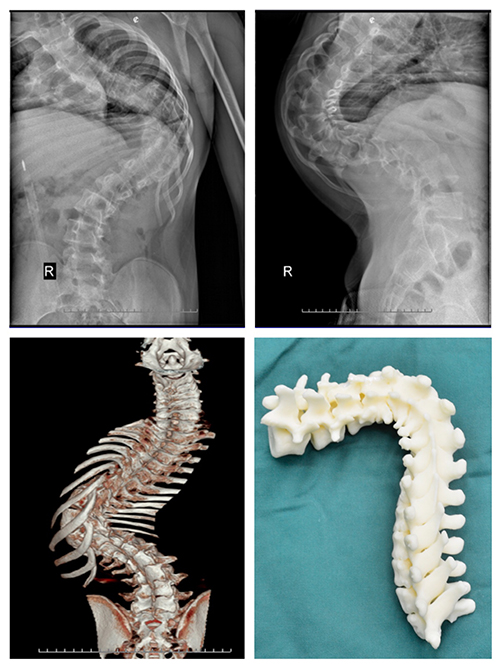

案例一:患者陶某,女,23岁,宣威市某幼教机构教师,于2006年(12岁)就开始出现双侧肩背部不等高,且逐年加重。她曾在家乡县医院就诊,被告知当时并无合适的治疗技术,只好回家任病情继续发展,有时做些针炙理疗等治疗,但效果并不太好。陶某上学时还能坚持进行体育运动,近年她同事发现她走路时有“喘息”声,提醒她最好再去医院看看。陶某虽然自己没发觉有不适,适逢了解到现在已有手术方式可以治疗此病,她决定来到飞禽走兽攻略站 进行手术治疗。

入院后,医生对她进行术前检查,发现陶某侧弯较重,侧弯Cob角达140°,后凸Cob角达105°。

此次飞禽走兽攻略站 骨科收治的两位患者,病史较长,病情严重,如果贸然进行矫形手术,可能术中脊髓神经牵拉过度出现下肢瘫痪;或者可能因脊柱小关节僵硬,导致矫形效果不满意。因此经飞禽走兽攻略站 骨科专家及省内其他专家会诊,两例患者术前均采用骨牵引办法,分别实施颅骨牵引及双侧股骨髁上骨牵引,牵引时间为4周,以松解小关节及神经根。牵引期间患者可坐起进食。

术后患者外观均有明显改善。

其中陶某侧弯Cob减小50°,后凸Cob角减小30°。